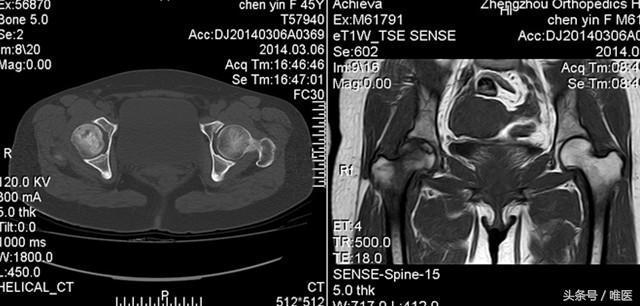

2、影像學(xué)檢查:醫(yī)生可能會(huì)通過(guò)X光、MRI等影像學(xué)檢查手段來(lái)確診股骨頭壞死。